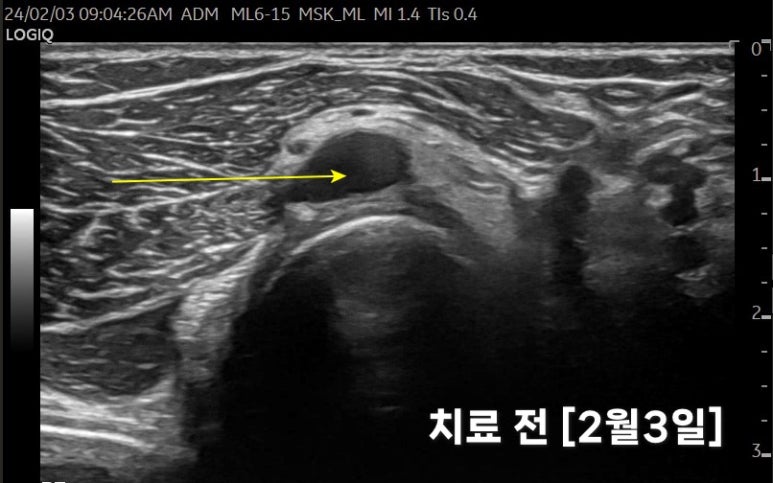

오늘 소개해드릴 케이스는

지난 2월 3일

강서구 화곡동에서 오신

40대 여자 환자분입니다.

평소 팔을 많이 쓰시는데

1달 전부터

우측 팔꿈치가 아프시다고요.

팔꿈치 관절과 연결된이 보입니다.

으로 표시한물혹이팔꿈치 관절과연결되어 있었는데요.

관절 염증으로 물 찬 것이

바깥으로 빠져나와

덩어리를 형성한 것입니다.

까만 물혹이요골신경을 위로 밀어올리는모습입니다.

증상이 많이 호전되셔서수삼리혈을로체크해봤습니다.

저번 초음파와

차이가 보이시나요?